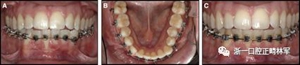

臨床檢查顯示固定保持器完好,弓絲沒有斷裂(圖13)。在下頜右側(cè)中切牙唇側(cè)和鄰近側(cè)切牙的舌側(cè)注意到有牙齦退縮。這些牙齒在退縮方向上存在顯著的扭矩差異。下頜的左側(cè)尖牙頰側(cè)錯(cuò)位,而右側(cè)尖牙舌側(cè)傾斜。三維射線照片證實(shí)了下頜右側(cè)尖牙面?zhèn)妊啦酃菃适?,右?cè)中切牙的喪失程度較輕。右側(cè)側(cè)切牙根也從舌側(cè)骨面上扭轉(zhuǎn)出來(圖14)。

圖13.粘合到尖牙和切牙上的柔性螺旋弓絲保持器,伴有牙齦退縮和附著喪失,中切牙之間嚴(yán)重的扭矩差異以及兩顆尖牙的橫向移動和扭矩。牙周問題和牙齒移動的嚴(yán)重程度均為牙周正畸聯(lián)合治療的指征:A,正面視圖; B,咬合面視圖。